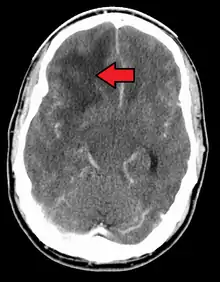

When viewed with MRI, glioblastomas often appear as ring-enhancing lesions. The appearance is not specific, however, as other lesions such as abscess, metastasis, tumefactive multiple sclerosis, and other entities may have a similar appearance.[51] Definitive diagnosis of a suspected GBM on CT or MRI requires a stereotactic biopsy or a craniotomy with tumor resection and pathologic confirmation. Because the tumor grade is based upon the most malignant portion of the tumor, biopsy or subtotal tumor resection can result in undergrading of the lesion. Imaging of tumor blood flow using perfusion MRI and measuring tumor metabolite concentration with MR spectroscopy may add diagnostic value to standard MRI in select cases by showing increased relative cerebral blood volume and increased choline peak, respectively, but pathology remains the gold standard for diagnosis and molecular characterization.